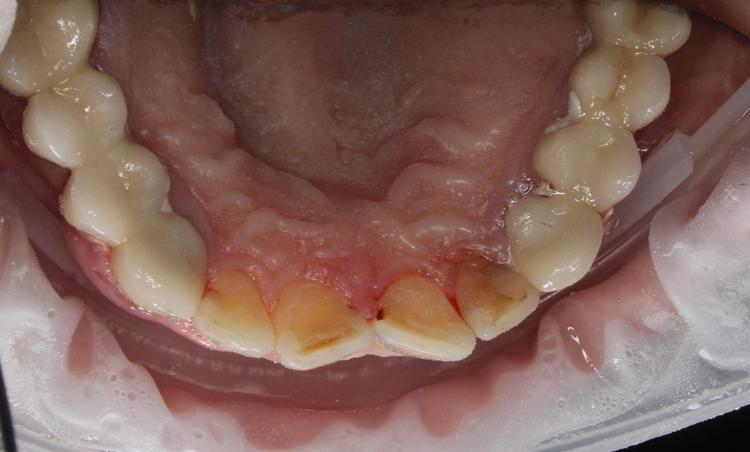

Профессиональная гигиена нижней фронтальной группы зубов фото доПрофессиональная гигиена нижней фронтальной группы зубов фото после

Посмотреть фото «до»

Профессиональная гигиена нижней фронтальной группы зубов

Во время процедуры удален пигментированный зубной налет и камень, проведена полировка зубов.